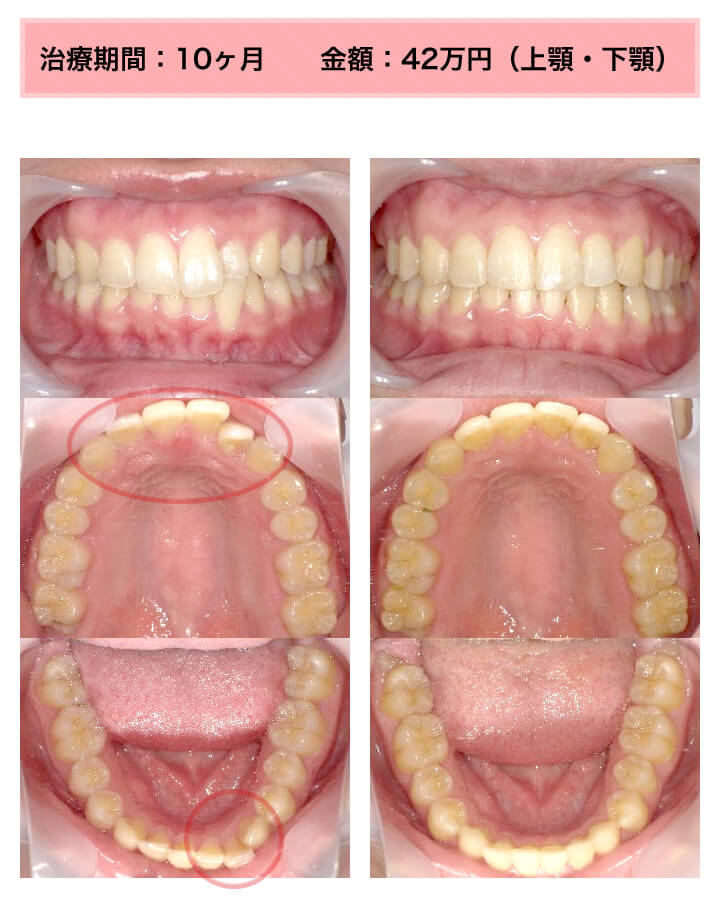

症例:上下顎の部分矯正

症例_002 前歯「捻転歯」症例

治療期間:10ヶ月金額:54万円+税30代女性少しのねじれ捻転歯前歯の突出感